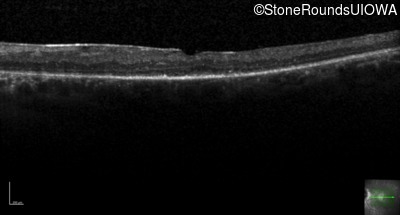

Optical Coherence Tomography - Left - 20/63 -1

Exemplar / OCT Stack

OCT Stack